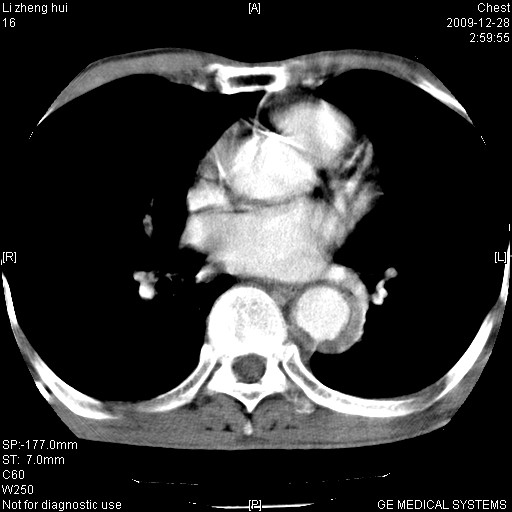

标题: CT23859:胸主动脉瘤 [打印本页]

标题: CT23859:胸主动脉瘤

男  79岁 胸部痛急诊入院,晚上做的增强

考虑主动脉瘤?(增粗、钙化、壁血栓?)

动脉瘤伴附壁血栓

1)考虑胸主动脉壁间血肿或夹层动脉瘤。2)多发性肝囊肿。

1)考虑胸主动脉附壁血栓或夹层动脉瘤。2)多发性肝囊肿。